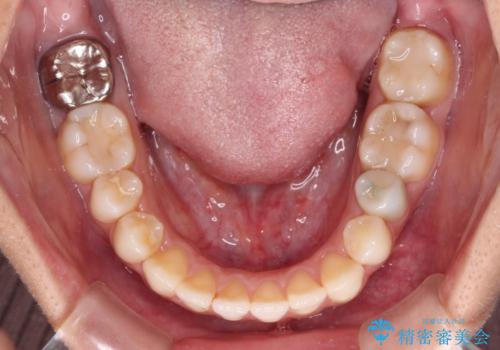

- オープンバイトのため、話しているときの見た目が気になるとのことで来院された患者様です。

下顎骨は左側にシフトしており、咬み合ったときには奥歯と前歯の一部しか接触していない状態でした。

骨格的な左右差は歯列矯正は改善できないため、上下歯列が全体的に接触することをゴールとしてインビザラインにて矯正治療を行うこととしました。

前歯のデコボコの解消と並行して上下の奥歯を圧下させるようにすることで、前歯を接触させるように計画しました。

上下の隙間に舌が入り込むことがオープンバイトの原因であったため、舌の筋肉のトレーニングも並行して行い、後戻りの抑制を図りました。